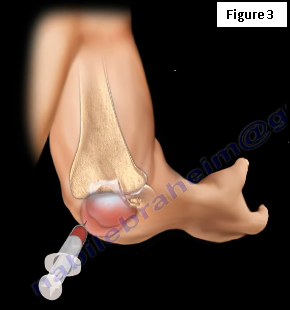

Treatment for elbow bursitis typically includes anti-inflammatory medications, antibiotics if an infection is suspected, ice therapy, and aspiration—the fluid should be sent away to be tested for cell count, cultures, and crystals (Figure 3). Surgery in the form of debridement and excision of the bursa may be necessary. Protective covering should be placed around the elbow while avoiding activities that aggravate the condition.